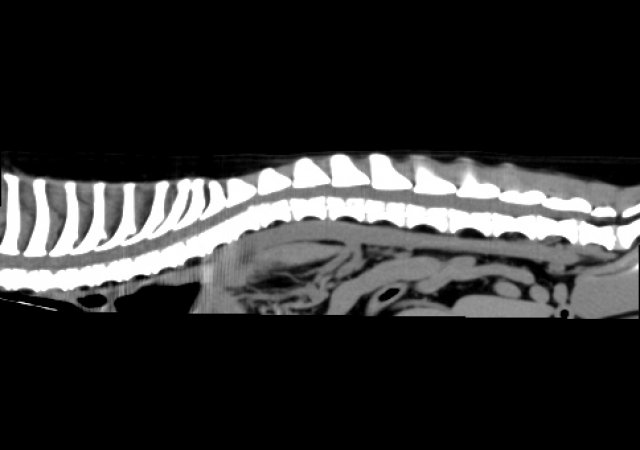

Bandscheibenvorfall (Diskopathie) und Lähmungen

Jeder Hund kann einen Bandscheibenvorfall bekommen, doch meist sind es die kleinen (chondrodystrophen) Hunderassen, wie beispielsweise Französische Bulldoggen, Dackel, oder Jack Russel Terrier, die zu uns kommen, weil sie schwankend laufen oder gar vollständig gelähmte Gliedmaßen haben. Gerade bei den gelähmten Patienten ist schnelles Handeln erforderlich. Für die Diagnose bietet unsere Praxis das unbedingt notwendige CT.

Nicht jeder Bandscheibenvorfall kann und muss operiert werden. Ist eine Operation notwendig, so ist es häufig die Operation mit einem Ventralslot (Halswirbelsäule), einer Hemilaminketomie (Brust- und Lendenwirbelsäule) oder einer dorsalen Laminektomie (Cauda Equina Compressionssyndrom).

CT Wirbelsäule